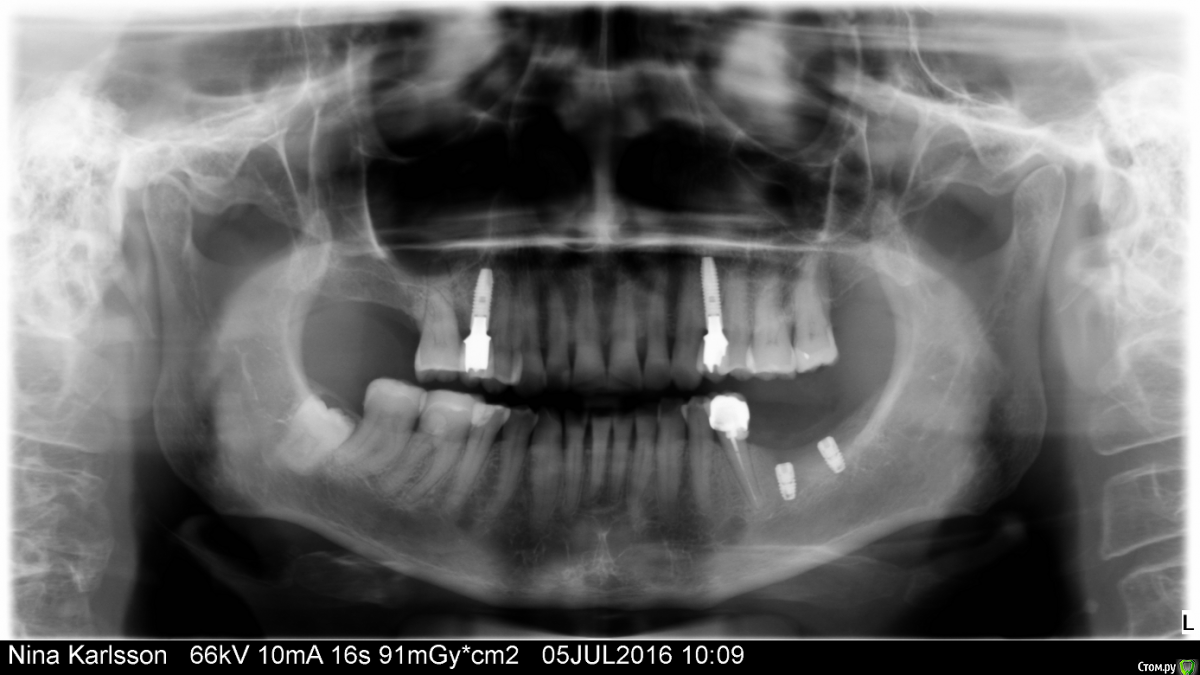

Поставлены два имплантата на нижней челюсти слева - 6, 7, снимок сделан непосредственно после операции. Планируется также замена коронки на депульпированной 5-ке.

Но есть серьезные проблемы с прикусом из-за повышенной истираемости эмали, передние зубы прямо таки крошатся и ломаются. Прблемы возникли и постепенно усилились после того, как несколько лет назад врач удалили 7 вверху справа, а затем установил коронку и накладку на нижние 6,7 справа. Высота их оказалась заниженной, прикус соотвественно тоже. А затем еще и нижние слева пришлось удалить (раньше тут стоял мост 5-7). Жевать пришлось только правой стороной с сильно заниженной высотой моляров.

Делать это очень неудобно, ВВС болит и голова тоже, передние зубы как бы мешают и соответственно потихоньку крошатся! Постален диагноз "артрит ВВС" слева.